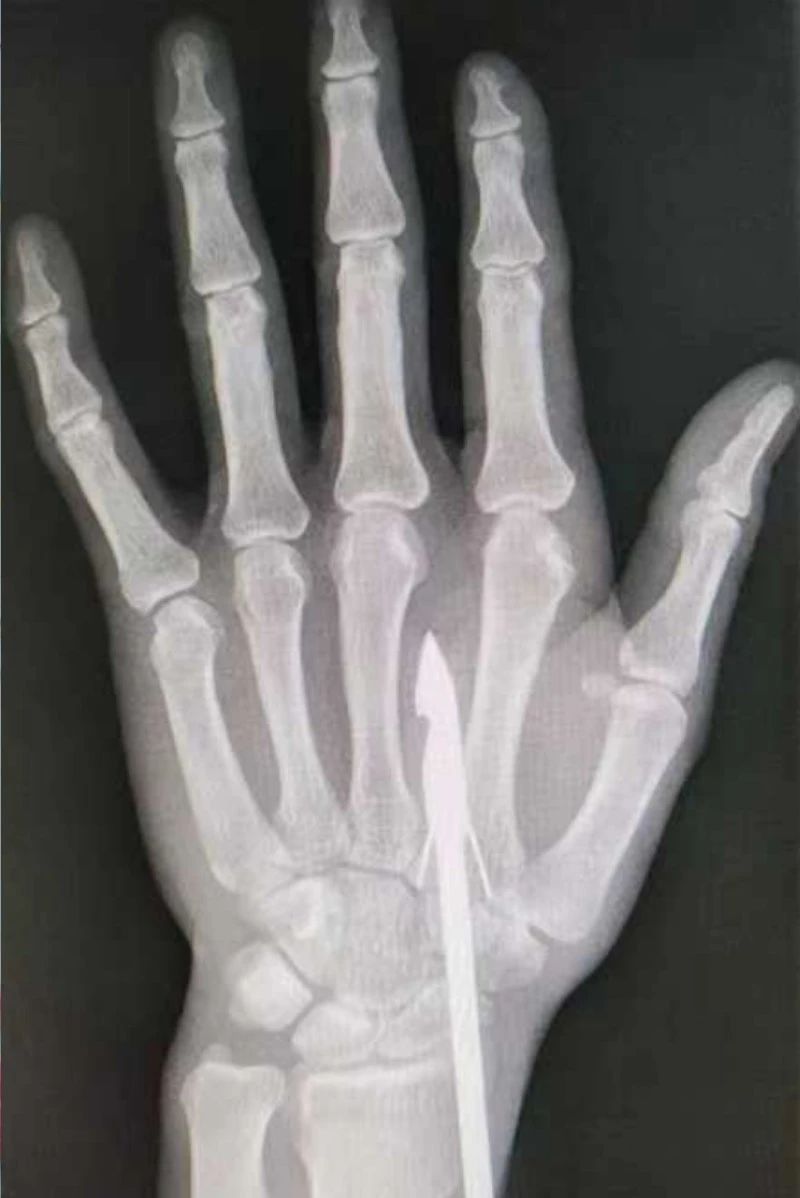

時(shí)間緊迫,每一秒的流逝都可能對(duì)傷者的手部功能造成不可逆的損害。接診醫(yī)生代彭威,迅速對(duì)傷者進(jìn)行了初步檢查。他注意到,魚鉤已經(jīng)深深嵌入皮膚,情況遠(yuǎn)比表面看起來(lái)復(fù)雜。沒有絲毫猶豫,立即安排了X線檢查以確認(rèn)魚鉤的位置及傷及范圍,以及急診化驗(yàn)檢查以評(píng)估患者的整體狀況。

確保在取出魚鉤的同時(shí),不對(duì)周圍的組織造成額外的傷害。8點(diǎn)15分左右患者在局部浸潤(rùn)麻下進(jìn)行手術(shù),經(jīng)探查后魚鉤未傷及重要血管、神經(jīng)及肌腱,經(jīng)過(guò)緊張的十分鐘,魚鉤終于被順利取出,隨后對(duì)傷口進(jìn)行了仔細(xì)的清理和縫合,用敷料仔細(xì)包扎,確保傷口能夠順利愈合。